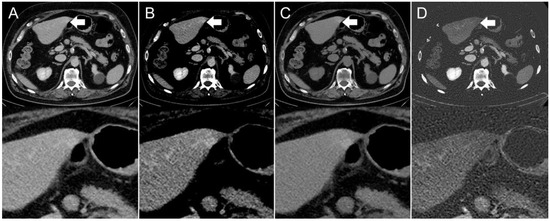

Figure 3. Axial contrast-enhanced CT scan of a 67-year-old man. Hyperdensity (indicated by arrows) on the left liver lobe in the (A,B) conventional 120 kVp image using an (A) abdomen window and (B) liver window, which might be interpreted as a hyperenhancing liver lesion. The (C) virtual non-contrast (VNC) image reconstruction and (D) iodine image reconstruction reveal that it is not a hyperenhancing liver lesion, but a streak artifact originating from the stomach antrum.

The presence of visible intestinal peristalsis-related streak artifacts on the liver was significantly lower (p < 0.001) in the iodine image reconstructions with 18/208 (9%) compared with the conventional 120 kVp images with 51/208 (25%) (see Figure 2, Figure 3 and Figure 4). The presence of visible peristalsis-related streak artifacts on the liver was not significantly lower in 40 keV monoenergetic image reconstructions with 48/208 (23%) (p = 0.15), 200 keV monoenergetic image reconstructions with 51/208 (25%) (p = 1.0), or VNC image reconstructions with 50/208 (24%) (p = 1.00) compared with conventional 120 kVp images.